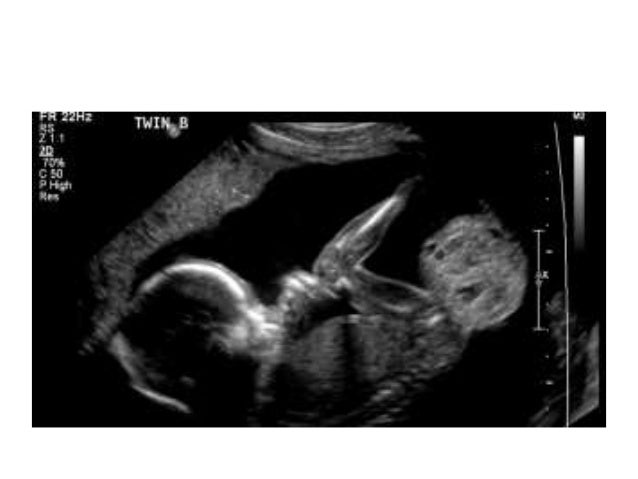

Тератома яичника при беременности на узи - фото презентация